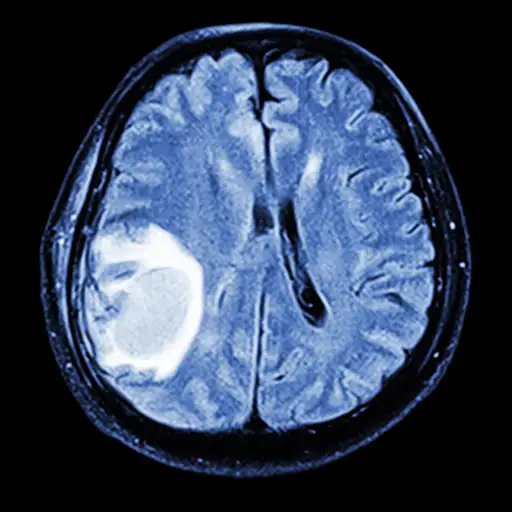

大脑中转移的迹象

症状可以从物理到心理学,并且可能包括:

- 头痛逐渐变得更糟,头部压力

- 模糊或双重视野

- 缉获

- 呕吐或恶心

- 讲话难以言论

- 行为,情绪或人格的变化